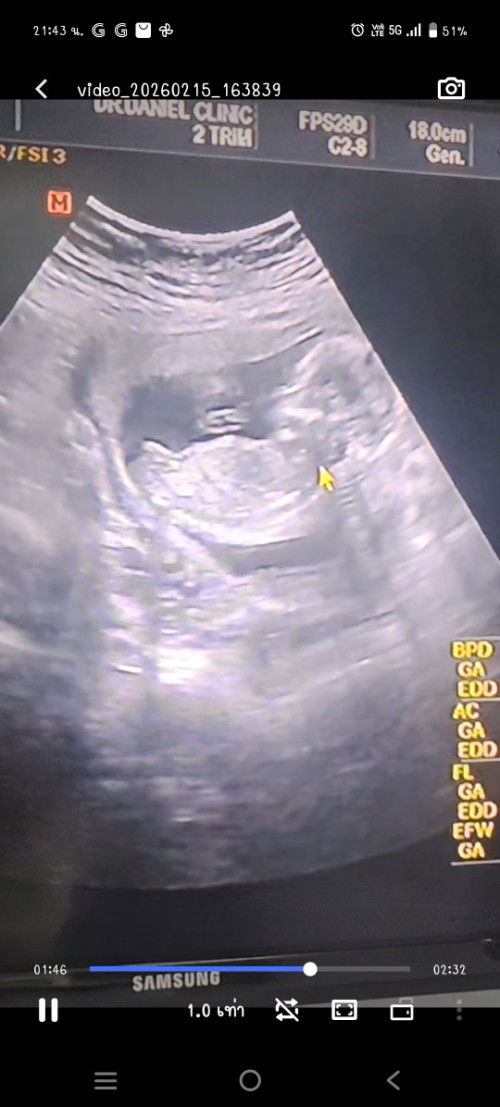

หมอได้ทำการ อัลตร้าซาวด์ ผ่านหน้าท้อง และ ช่องคลอด ในเครื่อง อัลตร้าซาวด์ บอกอายุครรภ์ว่า 7 สัปดาห์ 6 วัน แต่ถุงการตั้งครรภ์จริงๆ เล็กมากๆ เจอไข่แดง ตั้งครรภ์ในมดลูกปกติ หมอนัดอีก 2 สัปดาห์ เพื่อมาอัลตร้าซาวด์ แบบนี้ ผิดปกติไหมคะ กังวลมากๆเลยคะ 😢🥺 รอบประจำเดือนคือ วันที่ 2 ธันวาคม หมดวันที่ 9 ธันวาคม พ.ศ. 2568 ระยะเวลา 8 วัน รอบเดือน ยาว 35 - 36 วัน เป็นไปได้ไหมคะ ที่ไข่จะตกช้า

พอดีตั้งครรภ์ 6 week 4วันค่ะ เมื่อวานไปอัลตร้าซาวมาเจอถุงไข่แดง เจอถุงตั้งครรภ์แล้วแต่ยังไม่เจอเบบี๋ค่ะ ประมาณกี่สัปดาห์ถึงจะเจอน้องคะ คุณแม่ใจแป้วเลยค่ะ 🥹❤️#ช่วยบอกกันหน่อยนะคะ #ท้องแรก